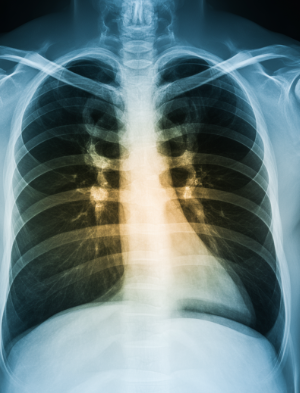

폐렴이 의심되면 보통 흉부 X-ray를 먼저 찍습니다. 필요할 경우 CT 촬영으로 더 정밀하게 확인하기도 해요. 혈액 검사로 염증 수치를 확인하고, 가래 검사를 통해 어떤 균이 원인인지 찾습니다. 정확한 진단을 위해서는 단순 증상만으로 판단하지 않고 여러 검사를 종합적으로 진행합니다.